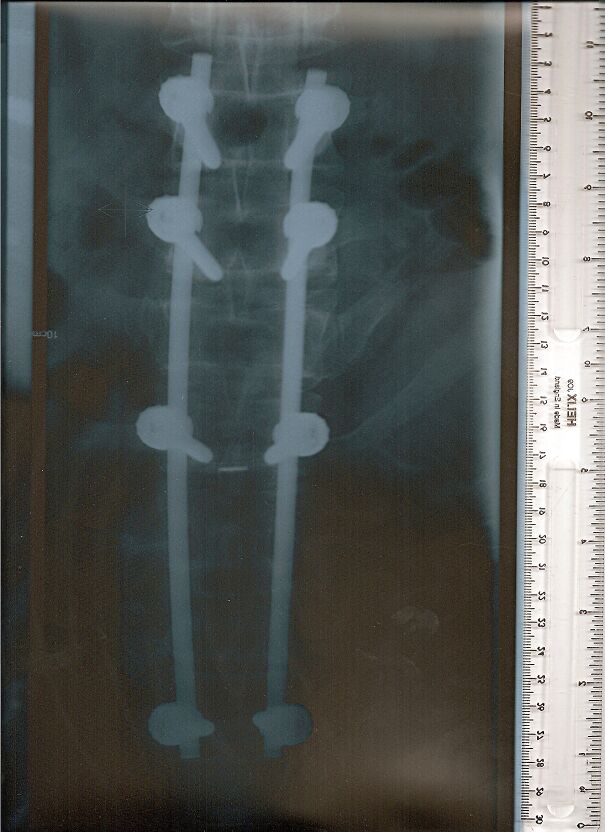

Before And After Surgery For Blount's Disease